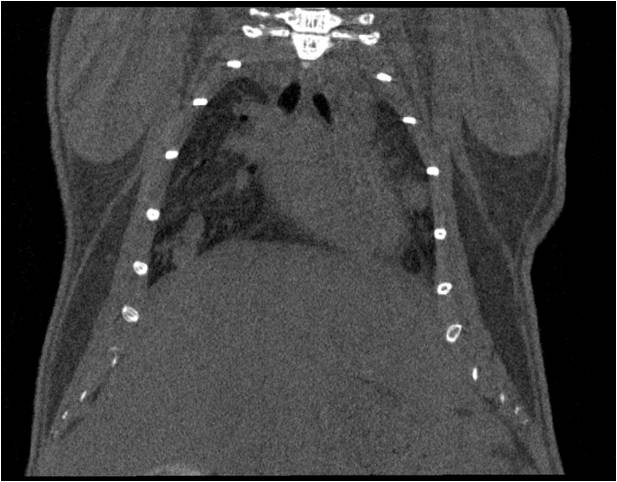

肺轉移

小鼠模式,22.5μm像素

正常

8天 14天